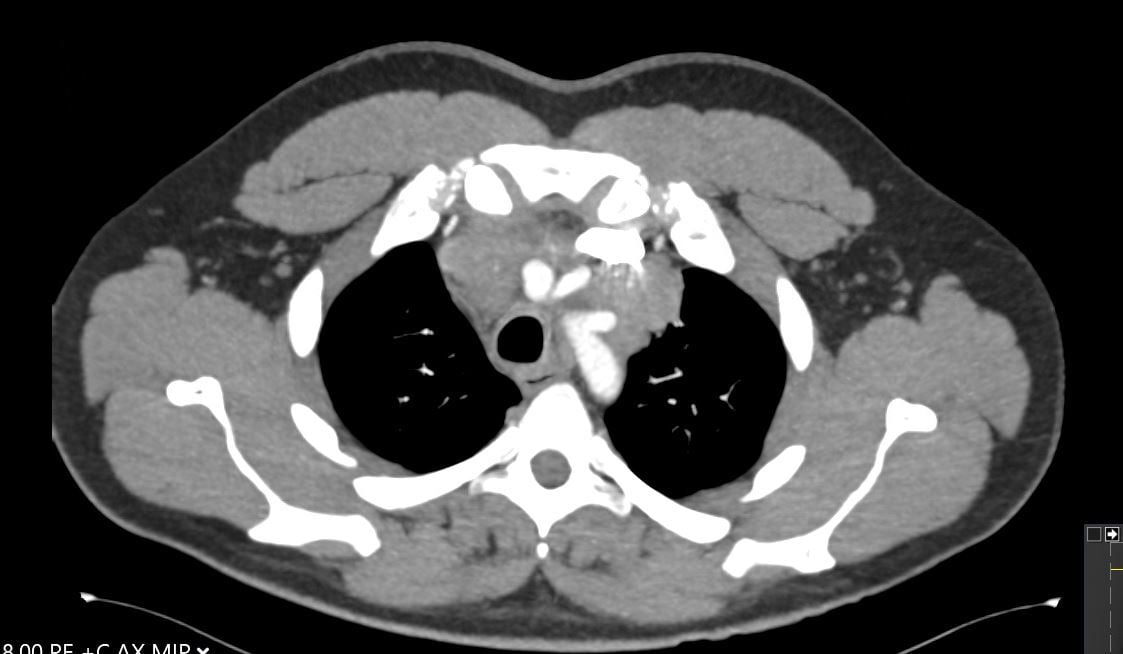

A 30-year-old man presents with dyspnea and is found to have an anterior mediastinal mass, as well as supraclavicular lymphadenopathy; biopsy of the mass is consistent with thymic carcinoma. Imaging shows his anterior mediastinal mass, lung and diaphragmatic lesions consistent with metastatic malignancy, and probable pericardial involvement with small pericardial effusion (Figures 1, 2, 3, and 4).

Fig. 2: CT image showing large mediastinal mass found to be thymic carcinoma. -

Fig. 3: CT image showing large mediastinal mass found to be thymic carcinoma. -